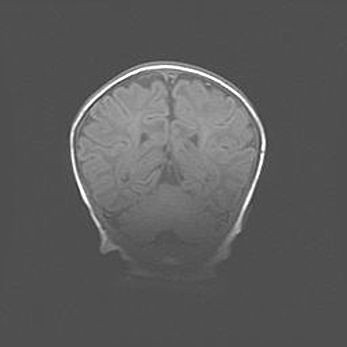

Открытая гидроцефалия.

Возраст: 6 месяцев 15 дней

Вес: 6200 г

Пол: женский

Окружность головы: 41 см

Срок гестации: 38 недель

Гидроцефалия головного мозга у новорожденных – это скопление избыточного количества цереброспинальной жидкости в головном мозге. Ее избыточное скопление в мозге приводит к патологическому расширению желудочков мозга (четырех полостей, расположенных в глубине белого вещества мозга, заполненных цереброспинальной жидкостью и связанных узкими проходами).

Открытый тип гидроцефалии (сообщающаяся) наблюдается тогда, когда нарушен механизм всасывания ликвора в системный кровоток. При этом типе причиной заболевания чаще всего является перенесенные ранее инфекции (например: менингит),  либо же наличие крови в субарахноидальном пространстве.